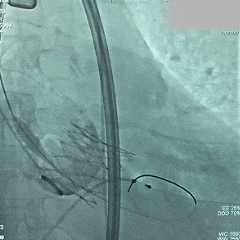

脱钩释放

脱钩后,瓣膜无位移

造影评估,瓣膜深度可,无瓣周漏

左头观察,腰征明显,锚定稳定